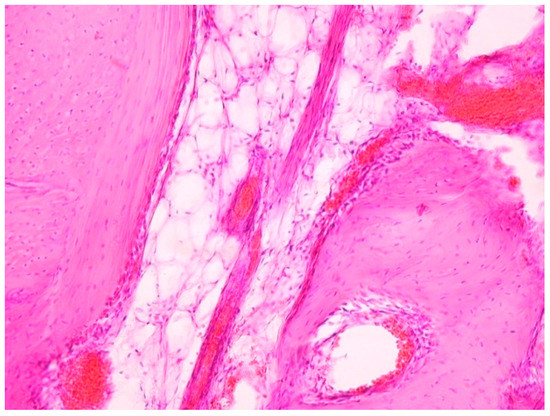

The results of the evaluation of contact osseogenesis in the first group of experimental animals showed that a part of the implant is surrounded by an intermediate layer of connective tissue, along the perimeter of which there is regenerating coarse-fibered bone tissue surrounded by laminar bone without the pronounced morphological organization usually characteristic of normal bone structure. Largely incomplete processes that lead to the production of laminar bone tissue with the formation of coarse-fibered bone, are still observable (Figure 7).

Figure 7. Morphological pattern of the tissue surrounding an implant of the first type. Individual trabecula of coarse-fibered bone. Two months after implantation. 400×.